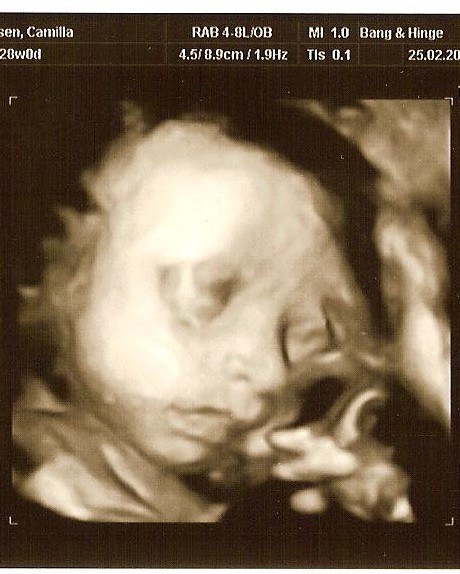

Selvom vores søn var lille, så havde han ikke meget plads at ligge på i uge 30, og da de ligger "lidt klemt", så blir det sværere at se noget, jeg større de blir. Vi fik nogen rigtig gode billeder, men det tog en del tid, fordi hans arme lå presset op foran hans ansigt og det er jo svært lige at flytte dem

Men sikke en stor oplevelse